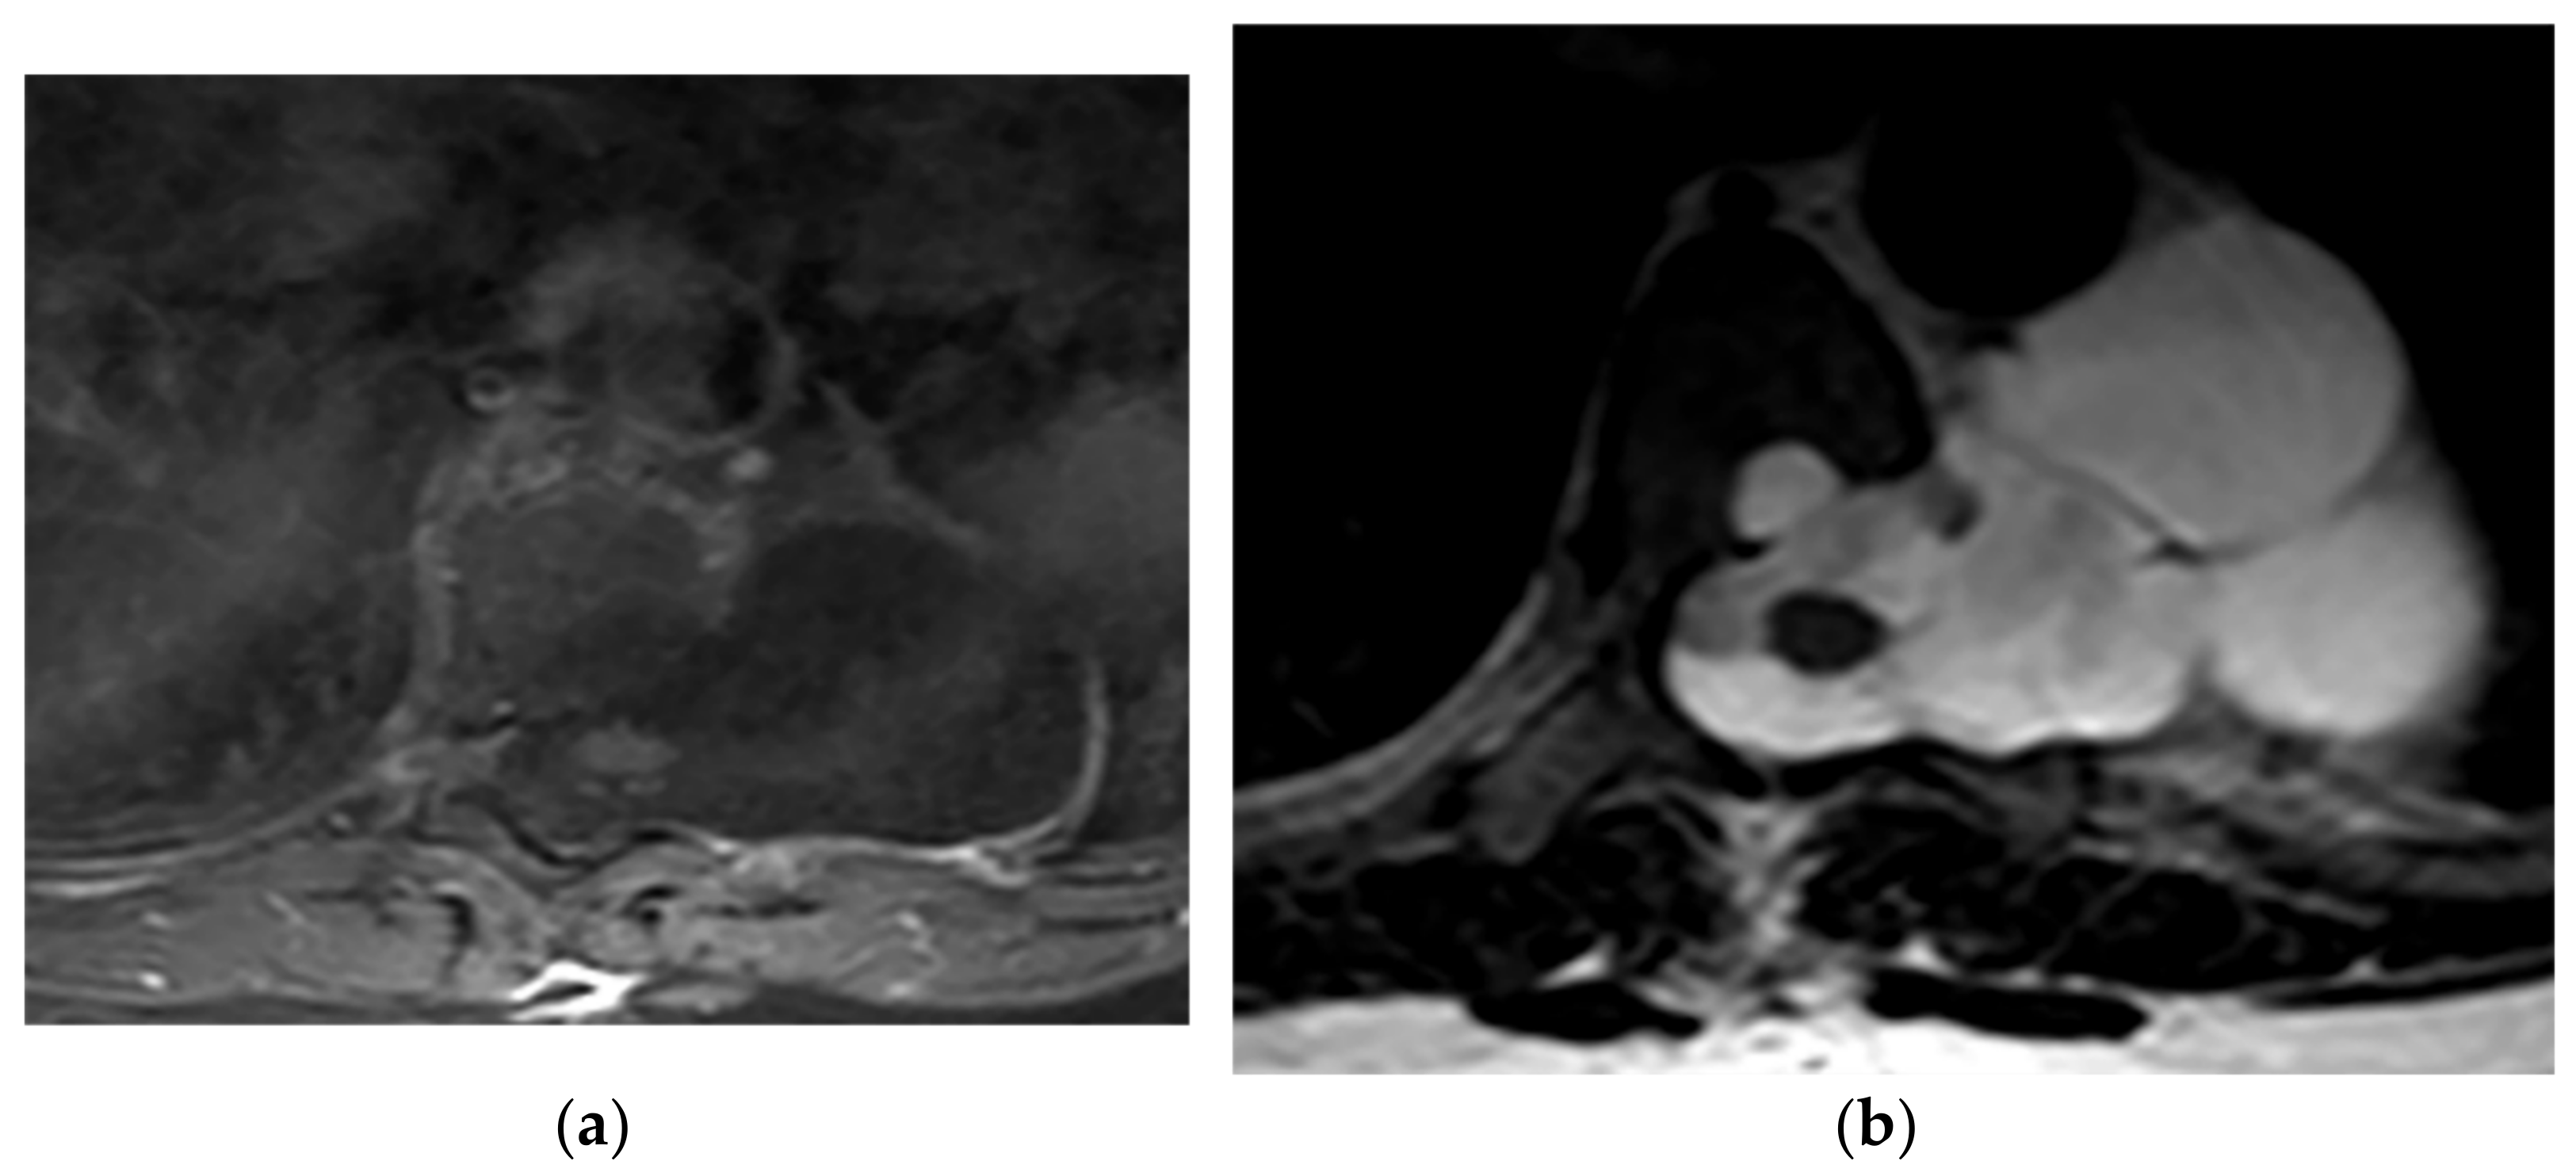

8.1. Pyogenic Spondylodiskitis

8.2. Tuberculosis Spondylodiskitis

- Hong, S.H.; Choi, J.-Y.; Lee, J.W.; Kim, N.R.; Choi, J.-A.; Kang, H.S. MR Imaging Assessment of the Spine: Infection or an Imitation? Radiographics 2009, 29, 599–612. [Google Scholar] [CrossRef]

- Ramadani, N.; Dedushi, K.; Kabashi, S.; Mucaj, S. Radiologic Diagnosis of Spondylodiscitis, Role of Magnetic Resonance. Acta Inf. Med. 2017, 25, 54–57. [Google Scholar] [CrossRef]

- Kumar, Y.; Gupta, N.; Chhabra, A.; Fukuda, T.; Soni, N.; Hayashi, D. Magnetic resonance imaging of bacterial and tuberculous spondylodiscitis with associated complications and non-infectious spinal pathology mimicking infections: A pictorial review. BMC Musculoskelet. Disord. 2017, 18, 244. [Google Scholar] [CrossRef]

- Yeom, J.A.; Lee, I.S.; Suh, H.B.; Song, Y.S.; Song, J.W. Magnetic Resonance Imaging Findings of Early Spondylodiscitis: Interpretive Challenges and Atypical Findings. Korean J. Radiol. 2016, 17, 565–580. [Google Scholar] [CrossRef]